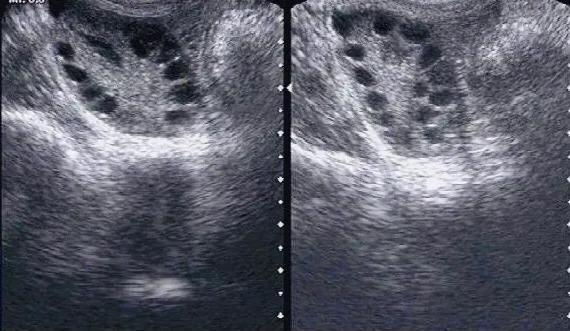

(3) 卵泡那么多,为何怀不上?

质量大于数量,多,但是不成熟,自然没有优势卵泡的产生,从而怀孕困难

提起多囊,很多人以为:我自己卵泡多,用促排药促排卵,不得长起来一大批卵泡吗?直接试管不方便快捷吗

其实,多囊促排会增加卵巢过渡刺激综合征的风险,所以这就说明促排一定寻找专业的医院,风险会降到最低

但是,即使获得卵子,也可能不够优质,受精卵发育成优质胚胎的数量也相对正常女性低。所以,试管并不是最好的办法